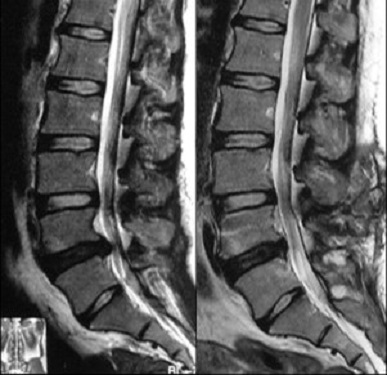

La HD lombaire consiste en l'expulsion d'un fragment de disque dans le canal rachidien. En cas de conflit avec les racines nerveuses, des symptômes douloureux sont ressentis dans les cuisses, jambes ou pieds. On parle alors de radiculalgie de type cruralgie ou sciatalgie.

La discopathie est le terme utilisé pour qualifier un disque intervertébral "usé". Les disques s'altérent avec le temps, ils se "déshydratent" et perde une partie de leurs propriétés mécaniques. Dans certains cas, cette dégradation est sévère ou rapide, sur un ou plusieurs niveaux, pouvant entrainer des douleurs lombaires.

Avec l'âge, de l'arthrose lombaire se développe. Des excroissances osseuses appelées "ostéophytes" peuvent apparaitre. Le ligament jaune peu également s'hypertrophier. S'ils sont trop développés, ils peuvent rétrécir le diamètre du canal et des foramens, comprimant les racines nerveuses. Des symptômes douloureux et une faiblesse, peuvent être ressentis dans les jambes, limitant la marche. On parle alors de claudication neurogène.